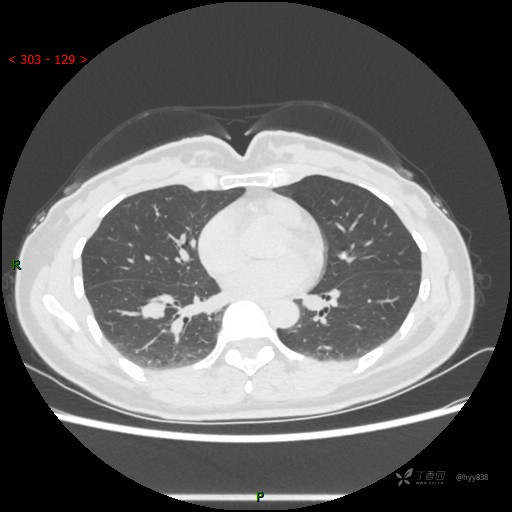

简要病史:患者2年前体检行胸部CT提示:右肺结节,当时结节较小,建议其定期复查,患者未在意。近期患者自觉呼气不畅,无畏寒发热,无咳嗽咳痰,无心慌胸闷胸痛,无头晕头痛,无腹痛腹泻,无四肢肌肉酸痛等不适,于当地医院行胸部CT提示:右肺下叶结节灶(18*10mm),现为求进一步诊治来我院就诊,门诊以“肺结节”收入我科。 自起病以来,患者精神、饮食、睡眠可,大小便正常,体力、体重未见明显异常。

辅助检查:CT

胸部CT平扫